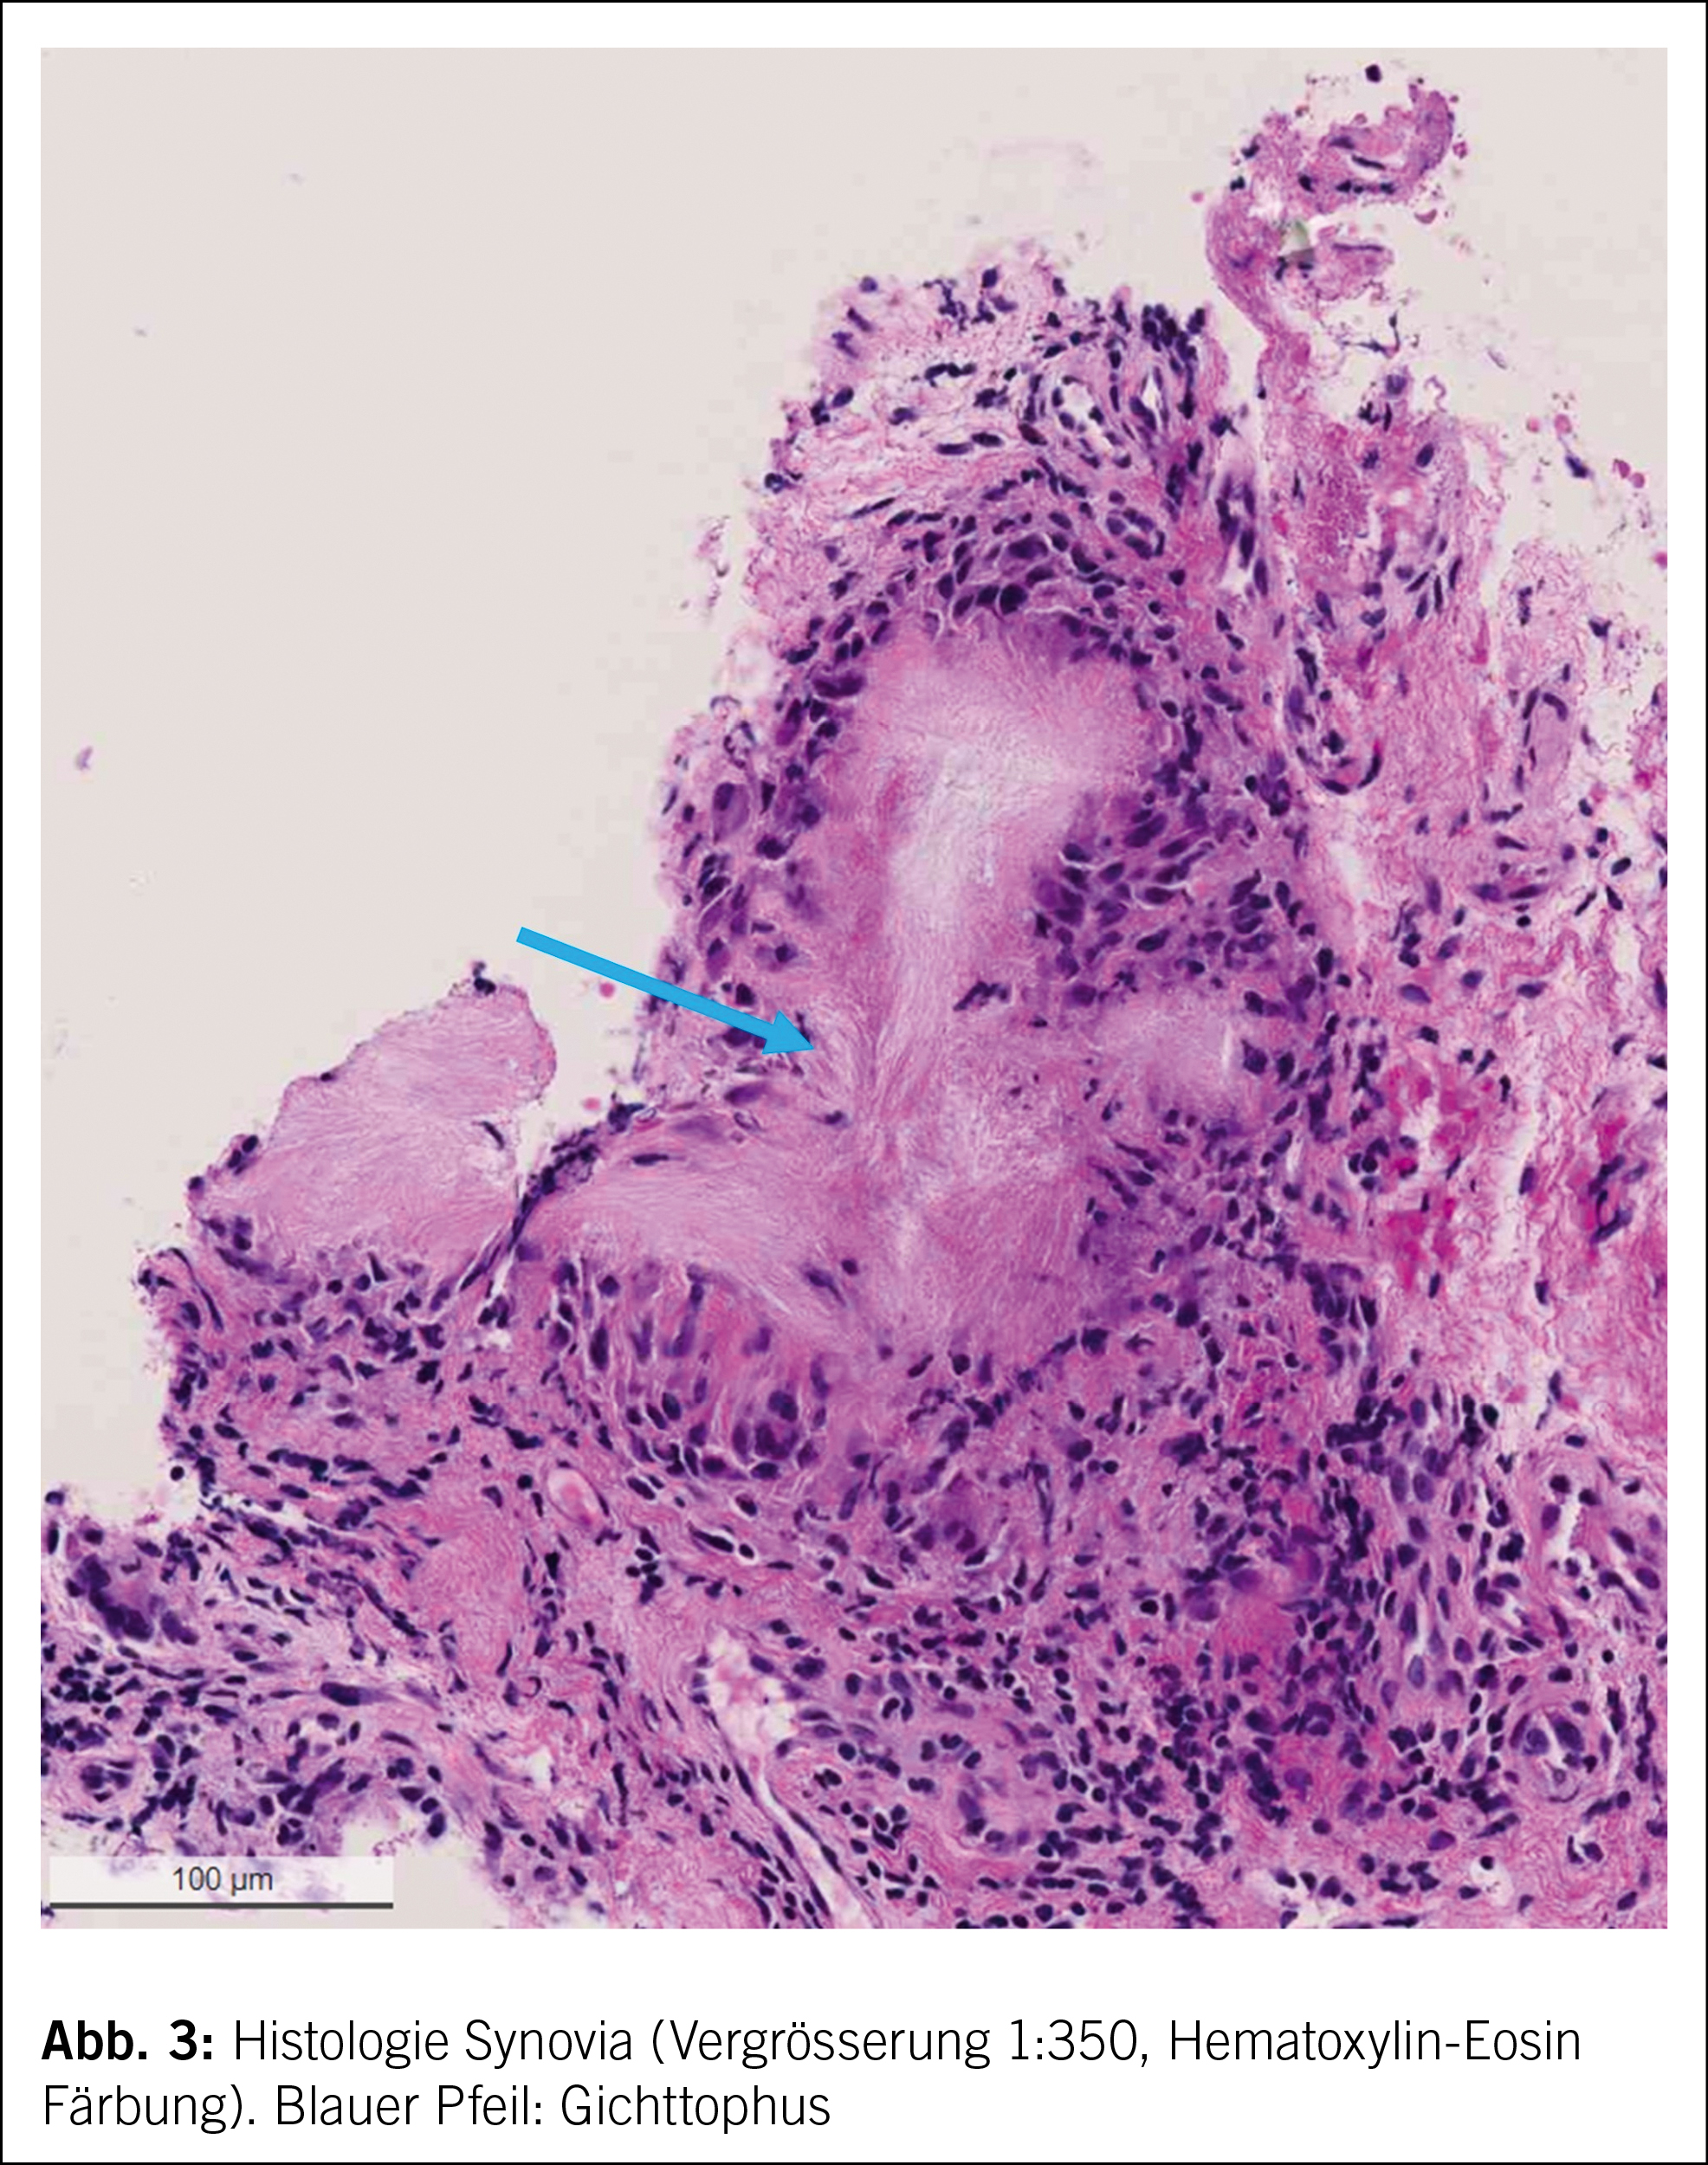

In der Pathologie wird das in Formalin fixierte Synovialgewebe entwässert und mit Paraffin infiltriert. Es werden 2uM dünne Gewebeschnitte für die histologische Beurteilung angefertigt. Die Standardfärbung ist Hematoxylin-Eosin (HE). Um mögliche Kristalle mittels polarisierten Lichts im Mikroskop darstellen zu können, wird ein Teil der Proben nach Entnahme direkt in 70% Ethanol und nicht Formalin fixiert.

Histologisch lassen sich auch an Formalin fixiertem Gewebe sog. Gichtthophi nachweisen, auch wenn die Kristalle herausgewaschen sein sollten während der Gewebeprozessierung im Labor (Abb. 3). Solche typischen Veränderungen zeigen eine faserige Grundsubstanz mit einem entzündlichen Randsaum (meist Histiozyten und Lymphozyten) auf. Somit konnte die Diagnose einer Gicht gestellt werden.